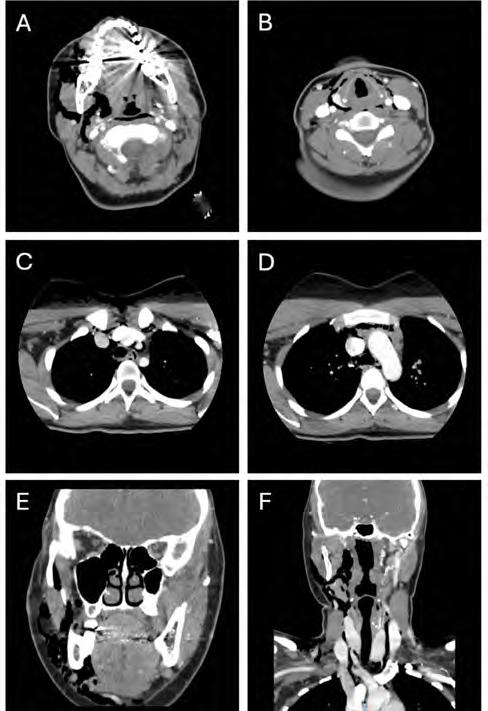

Laboratory findings upon presentation were significant for a white blood cell count of 16.29 x 109/L. Maxillofacial, neck and chest CTs with contrast were taken, revealing subcutaneous and deep soft-tissue emphysema extending from the right masticator space, through the superficial and deep fascial planes of the neck, into the retropharyngeal space and inferiorly into the mediastinum (Figure 2). The patient was admitted for observation and received intravenous clindamycin. An esophagram was ordered to rule out esophageal perforation.

Figure 2. Maxillofacial, neck, chest CT images on initial presentation. A through F, revealing extensive subcutaneous emphysema within deep spaces of neck and mediastinum.

Air and infection must travel through a series of deep spaces of the head and neck to reach the mediastinum. Dissecting air that initially enters the submandibular space freely travels to the masticator space. From there, it can cross through the buccopharyngeal gap wherein the styloglossus passes between the superior and middle pharyngeal constrictors and reaches the lateral pharyngeal space. The lateral pharyngeal space communicates with the retropharyngeal space, which exists between the buccopharyngeal fascia and the alar fascia. The alar fascia separates the retropharyngeal space from the danger space and merges with the buccopharyngeal fascia at the level of C6-T4 inferiorly. As the alar fascia is thin, it may be difficult to visualize on cross-sectional imaging in healthy patients and, thus, the retropharyngeal and danger spaces may appear as a singular space. Air that reaches the danger space may enter the mediastinum, potentially leading to airway compromise, pneumomediastinum, pneumopericardium and mediastinitis.[5]